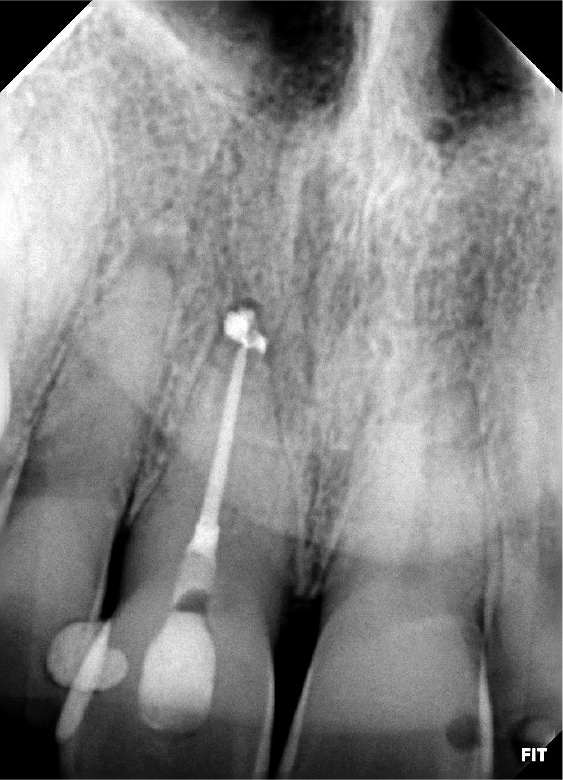

Raio-X inicial

Raio-x final